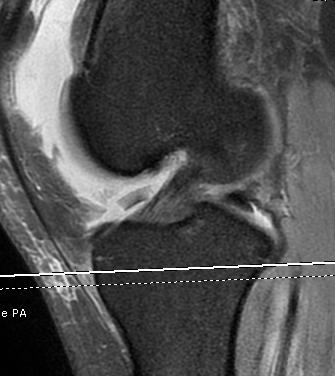

Medial Patellofemoral Ligament (MPFL)

- from MFC between femoral epicondyle and adductor tubercle

- to superolateral border patella

- deep to retinaculum / superficial to capsule

Usually tears off femur

Acts as a checkrein to lateral patella subluxation

- will usually be torn in all patients with patella dislocation

Open Technique

Very important to determine if torn from patella or medial epicondyle

- MRI very useful